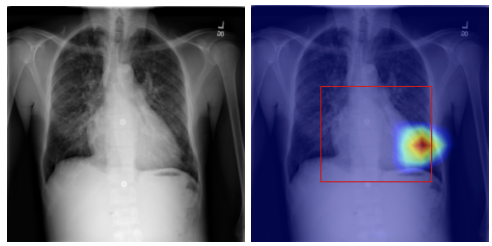

Explainable Artificial Intelligence Recommender Systems and Intelligent User Interfaces Information Visualization AI applied to the Medical domain